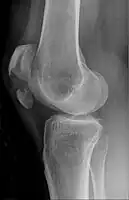

Comminuted fracture of patella